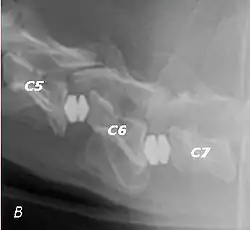

Wobbler disease is probably inherited in the Borzoi, Great Dane, Doberman, and Basset Hound.[2] Instability of the vertebrae of the neck (usually the caudal neck) causes spinal cord compression. In younger dogs such as Great Danes less than two years of age, wobbler disease is caused by stenosis (narrowing) of the vertebral canal[3] related to degeneration of the dorsal articular facets and subsequent thickening of the associated joint capsules and ligaments.[1] A high-protein diet may contribute to its development.[4] In middle-aged and older dogs such as Dobermans, intervertebral disc disease leads to bulging of the disc or herniation of the disc contents, and the spinal cord is compressed.[3] In Great Danes, the C4 to C6 vertebrae are most commonly affected; in Dobermans, the C5 to C7 vertebrae are affected.[5]

T2 weighted MRI in neutral (A) and linear traction (B) of a seven-year-old Doberman with a two-year history of cervical pain treated with NSAIDs and presented acutely tetraplegic: A C6-C7 and C5-C6 traction responsive myelopathy are evident on MRI. The spinal-cord hyperintensity seen at the C5-C6 is suggestive of chronic lesion and most likely responsible for the chronic history of cervical pain, while the C5-C6 lesion was most likely responsible for the acute tetraplegia.

Same dog (A) treated with double implant (B) three days after surgery: The dog became ambulatory three days after surgery. Four weeks after surgery, it had ataxia without conscious proprioceptive deficits, and three months after surgery, the dog was neurologically normal. The owner reported it had been two years since the dog was able to hold its neck in an elevated position.